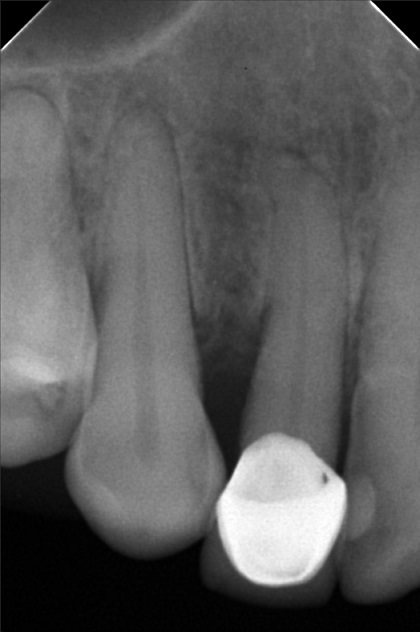

- 6/1/22- perio Tx / deep scaling laser curettage/ laser hypersensitivity/ next meeting FIRST WK august ***for change crown 9/10/22- stain removal 9/17/22 - check up for change crown

- rosario_03.jpg